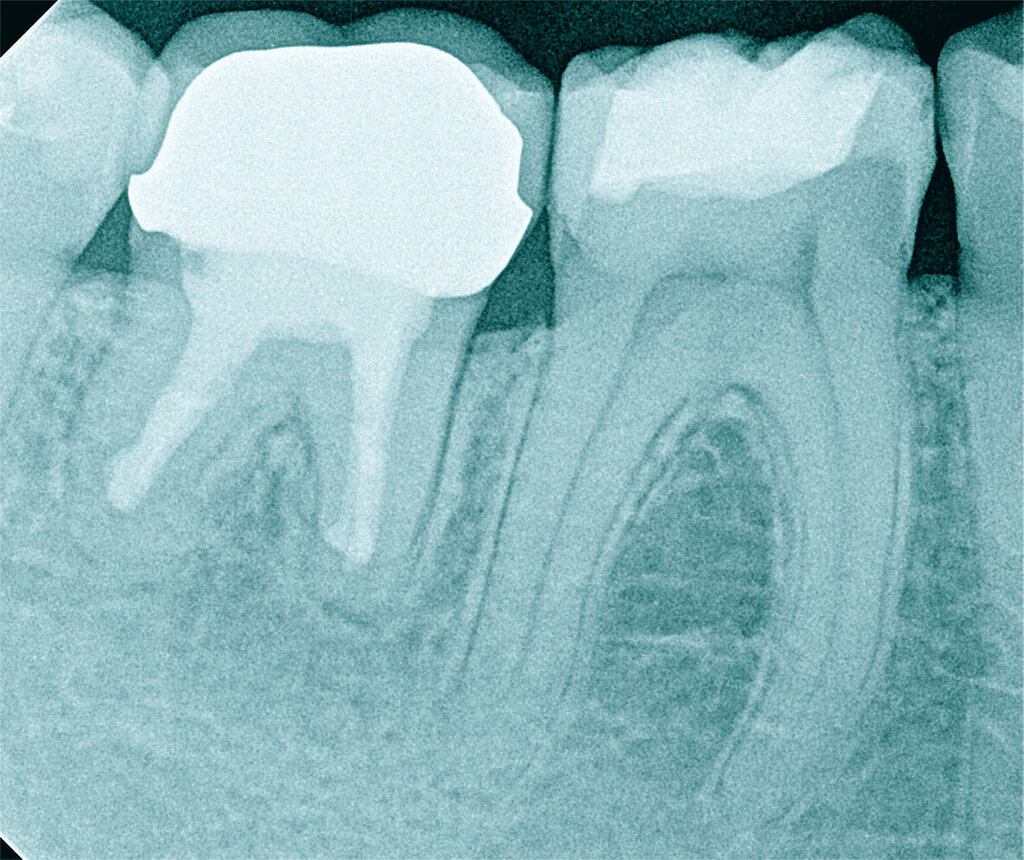

Röntgenbilder können genutzt werden, den anatomischen Schwierigkeitsgrad zu ermitteln. Lässt sich ein Wurzelkanal vollständig bis zum Apex mit einem Krümmungswinkel bis zu 30 Grad und einem großen gleichmäßigen Krümmungsradius erkennen, ist keine erhöhte Schwierigkeit in der Therapie zu erwarten (Abbildungen 1 und 2).

Krümmungsradius: Ist demgegenüber der Verlauf des Wurzelkanals unterbrochen, kann meist mit einer tiefen Wurzelkanalaufteilung gerechnet werden (Abbildung 3) [Reuver, 2002].